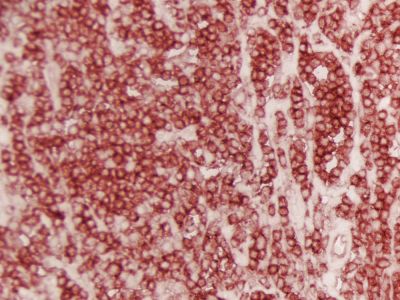

The peroxidase micropolymers of the ImmPRESS HRP polymer reagent limit steric interference and provide enhanced accessibility to the target, avoiding the disadvantages of other polymer systems that use large dextrans or other macromolecules as backbones. The result is crisp, strong staining of antibody targets, especially nuclear and membrane antigens (such as Ki67, estrogen receptor, bcl-2, CD3, CD8 and CD10) and greater sensitivity than other polymer systems.

The staining procedure is simple as shown in the diagram below. Following a blocking step with the diluted normal horse serum, sections are incubated with primary antibody. After a brief wash, the appropriate ImmPRESS Reagent is added to the sections and incubated for 30 minutes. Sections are again rinsed and the slides are developed with the peroxidase substrate of choice.